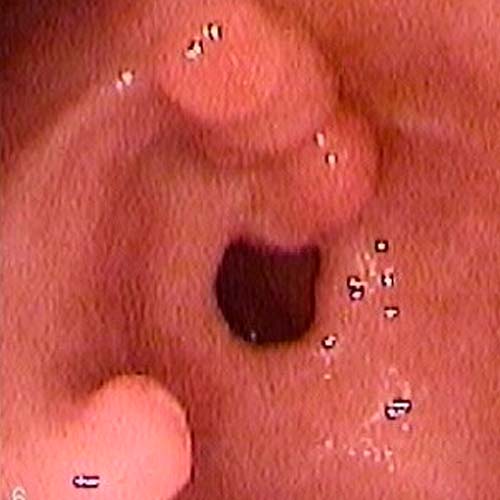

Procedimientos para visualizar el colon, tanto lumen como la mucosa, para tomar biopias o efectuar extirpación de pólipo, dilataciones, detención de un sangramiento y otras.

mediante una endoscopía digestiva alta permite observar directamente el estómago para detectar lesiones, tomar biopsias y confirmar o descartar cáncer de esófago, estomago y colon.